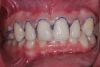

(6.) Posttreatment retracted close-up view of the composite veneers after they were placed with a self-adhesive resin cement.

Figure 6